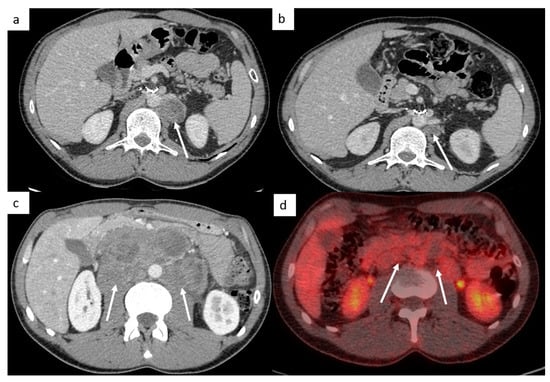

The retroperitoneal lymph nodes are the most common sites for TGCT (Figure 1). CT imaging remains the standard modality used for assessment of lymph node involvement, distinguishing between stages II (retroperitoneal nodes considered as regional lymph nodes) and III (supra-diaphragmatic nodes considered as metastatic disease) [21].

Figure 1.

Most common sites of lymph nodes and metastases in testicular cancer. Abdominal computed tomography (CT) shows retroperitoneal paraaortic lymph nodes (a, arrow). Thoracic CT reveals left supraclavicular lymph node (b, arrow). Thoracic CT demonstrates posterior mediastinal lymph nodes (c). Thoracic CT scan shows lung metastases appearing as multiple lung nodules (d).

The M stage defines the presence of distant metastatic disease, including distant lymph nodes outside the retroperitoneum. TGCT can spread above the diaphragm to the posterior mediastinum via the thoracic duct, it is therefore very important to analyze this region (Figure 1). NSGCT have a more random spread involving the anterior mediastinum, aortopulmonary window, hilar, supraclavicular and neck lymph nodes [33].

This M stage is most often present in choriocarcinoma and yolk sac tumors because of their hematogenous dissemination. The most common metastatic site of solid organs is the lungs. Most of the time, lung metastases appear as multiple lung nodules (Figure 1).

Other sites include liver, bones and rarely, testicular metastasis may occur to adrenals, kidneys, spleen, pleura, pericardium, peritoneum or retroperitoneum in very advanced disease (Figure 2). In case of large retroperitoneal lymph nodes, an extension may occur into the inferior vena cava in the form of tumor thrombus (Figure 2).

Figure 2.

Other sites of metastatic disease. In advanced stages, abdominal CT can show different sites of metastases including liver ((a,b), black arrows), peritoneal carcinomatosis ((b), white arrows), retroperitoneal carcinomatosis (c), cutaneous metastases in front of pubis (d). In case of large retroperitoneal lymph nodes ((e), white arrows), a tumor thrombus in the inferior vena cava can be found ((e), black arrows). Spinal bone CT shows several vertebral metastases (f).